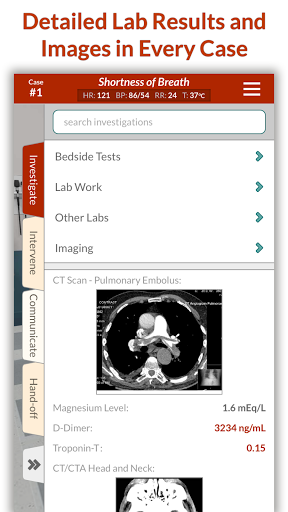

- Giá trị phòng thí nghiệm Phạm vi bình thường -

Giá trị phòng thí nghiệm bằng số hiện nay cách phạm vi bình thường cho bệnh nhân của bạn.